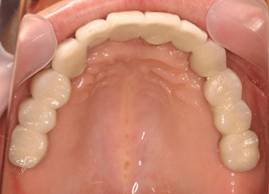

上顎

術後。上部構造はハイブリッドレジンです。しっかり嚙めるようになり喜んでいただきました。

上部構造装着後6年。ハイブリッドレジンを使用したため、少し艶がなくなってきました。上部構造の材料には金属、ハイブリッドレジン、セラミックなどがあります。セラミックはきれいですが欠けやすいため、最近はフルジルコニアを使っています。

上顎 少しすり減ってきました。